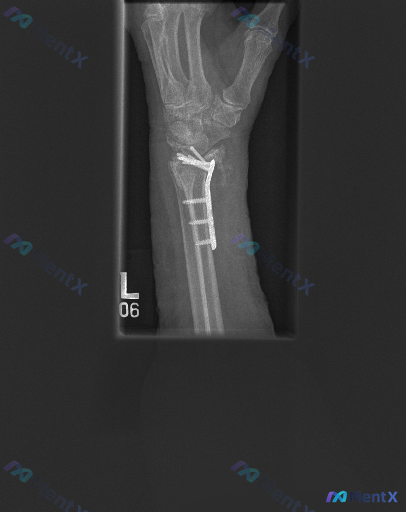

左侧桡骨远端骨折术后随访,无额外补充的急性症状或全身表现。

- 桡骨远端掌侧可见解剖锁定钢板及多枚螺钉固定,位置位于掌侧皮质表面

- 桡骨远端可见陈旧性骨折痕迹,骨折线区域已愈合,骨小梁结构基本连续

- 舟状骨、月骨等腕骨轮廓清晰,未见明显骨折或脱位,各腕骨相对位置基本正常

- 尺骨远端形态完整,下尺桡关节对位尚可

- 桡腕关节间隙清晰,诸骨排列关系尚可,侧位无明显倾斜畸形

- 腕关节周围软组织轮廓清晰,未见明显肿胀,未见异常高密度异物影或钙化灶